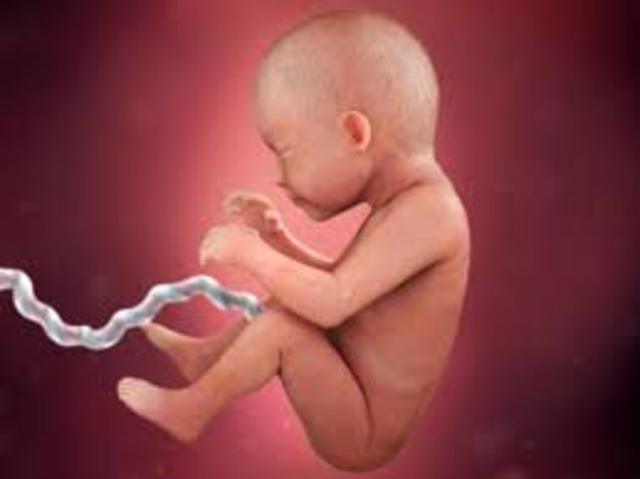

Fetus- An unborn offspring more than eight weeks after conception.

• 3rd Trimester

Length of Time: 28-40 weeks.

• 7th Month

7th Month

1. The baby can cry.

2. The baby can suck their thumb.

3. The baby can open their eyes.

• 8th Month

8th Month

1. The baby gains 2-3 pounds.

2. The baby moves their head into the down position.

3. The baby's lungs are fully developed.

• 9th Month

9th Month

1. The baby is 14-15 inches long.

2. The baby weighs 6-8 pounds.

3. The fetus acquires antibodies from mother.